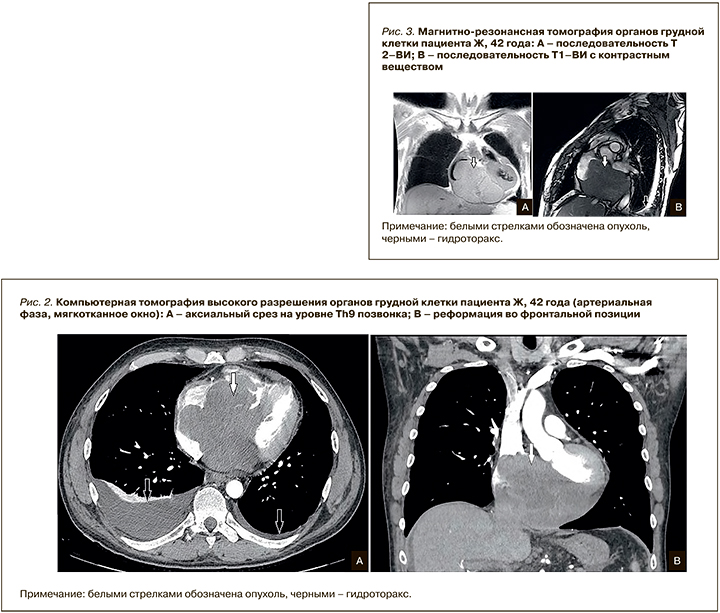

На серии срезов КТ высокого разрешения (КТВР) органов грудной клетки с контрастным препаратом (Омнипак 300 мг/мл – 60 мл) выявлено объемное образование неоднородной структуры с наличием гиподенсных участков и зон мягкотканной плотности, участков гиперваскуляризации во всех камерах сердца, преимущественно в правых отделах (рис. 2). Отмечено прорастание межпредсердной и межжелудочковой перегородки мягкотканными структурами с истончением стенок обоих предсердий. В структуре мягкотканных масс определяются единичные кальцинаты. В плевральных полостях с обеих сторон выявляется жидкость справа до 500 мл, слева до 80 мл. Легкие воздушны, без очаговых и инфильтративных изменений. Трахея, бронхи с обеих сторон обычного калибра, просвет сохранен, стенки бронхов не утолщены. Внутригрудные лимфатические узлы не увеличены.

Результаты МРТ органов грудной клетки с контрастированием (рис. 3): в полости сердечной сумки, преимущественно по диафрагмальной поверхности сердца и вдоль правых отделов, определяется объемное образование неправильной формы, с бугристыми контурами, преимущественно изоинтенсивного магнитно-резонансного сигнала. Образование приводит к сдавлению правых отделов сердца, распространяется в правую атриовентрикулярную борозду, на фиброзное кольцо и створки трикуспидального клапана с его обструкцией. Меньшее по объему, но схожее по магнитно-резонансной картине образование визуализируется в полости перикарда вдоль передней стенки левого желудочка. При введении контрастного препарата образования накапливают контрастное вещество.